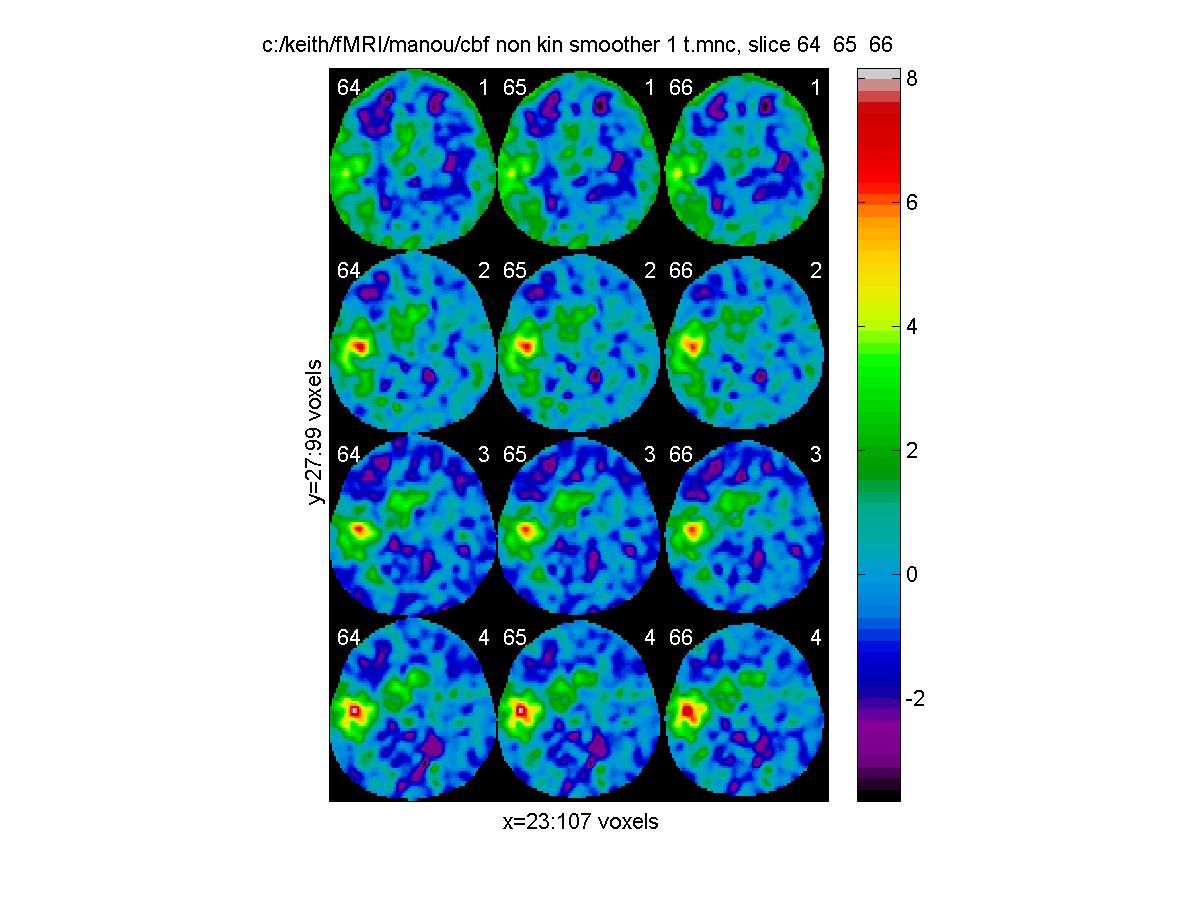

Or we might want to compare the t statistics on all tasks at a range of slices (64 65,66) that cover the region of greatest activation (rows are tasks, columns are slices):

m=['c:/keith/fMRI/manou/cbf_non_kin_smoother_1_t.mnc';

'c:/keith/fMRI/manou/cbf_non_kin_smoother_2_t.mnc';

'c:/keith/fMRI/manou/cbf_non_kin_smoother_3_t.mnc';

'c:/keith/fMRI/manou/cbf_non_kin_smoother_4_t.mnc']

clf;

view_slices(m,mask,0.65,64:66,1:4)

![[Click to enlarge image]](figs_pet_tn/fignormt1234.jpg)